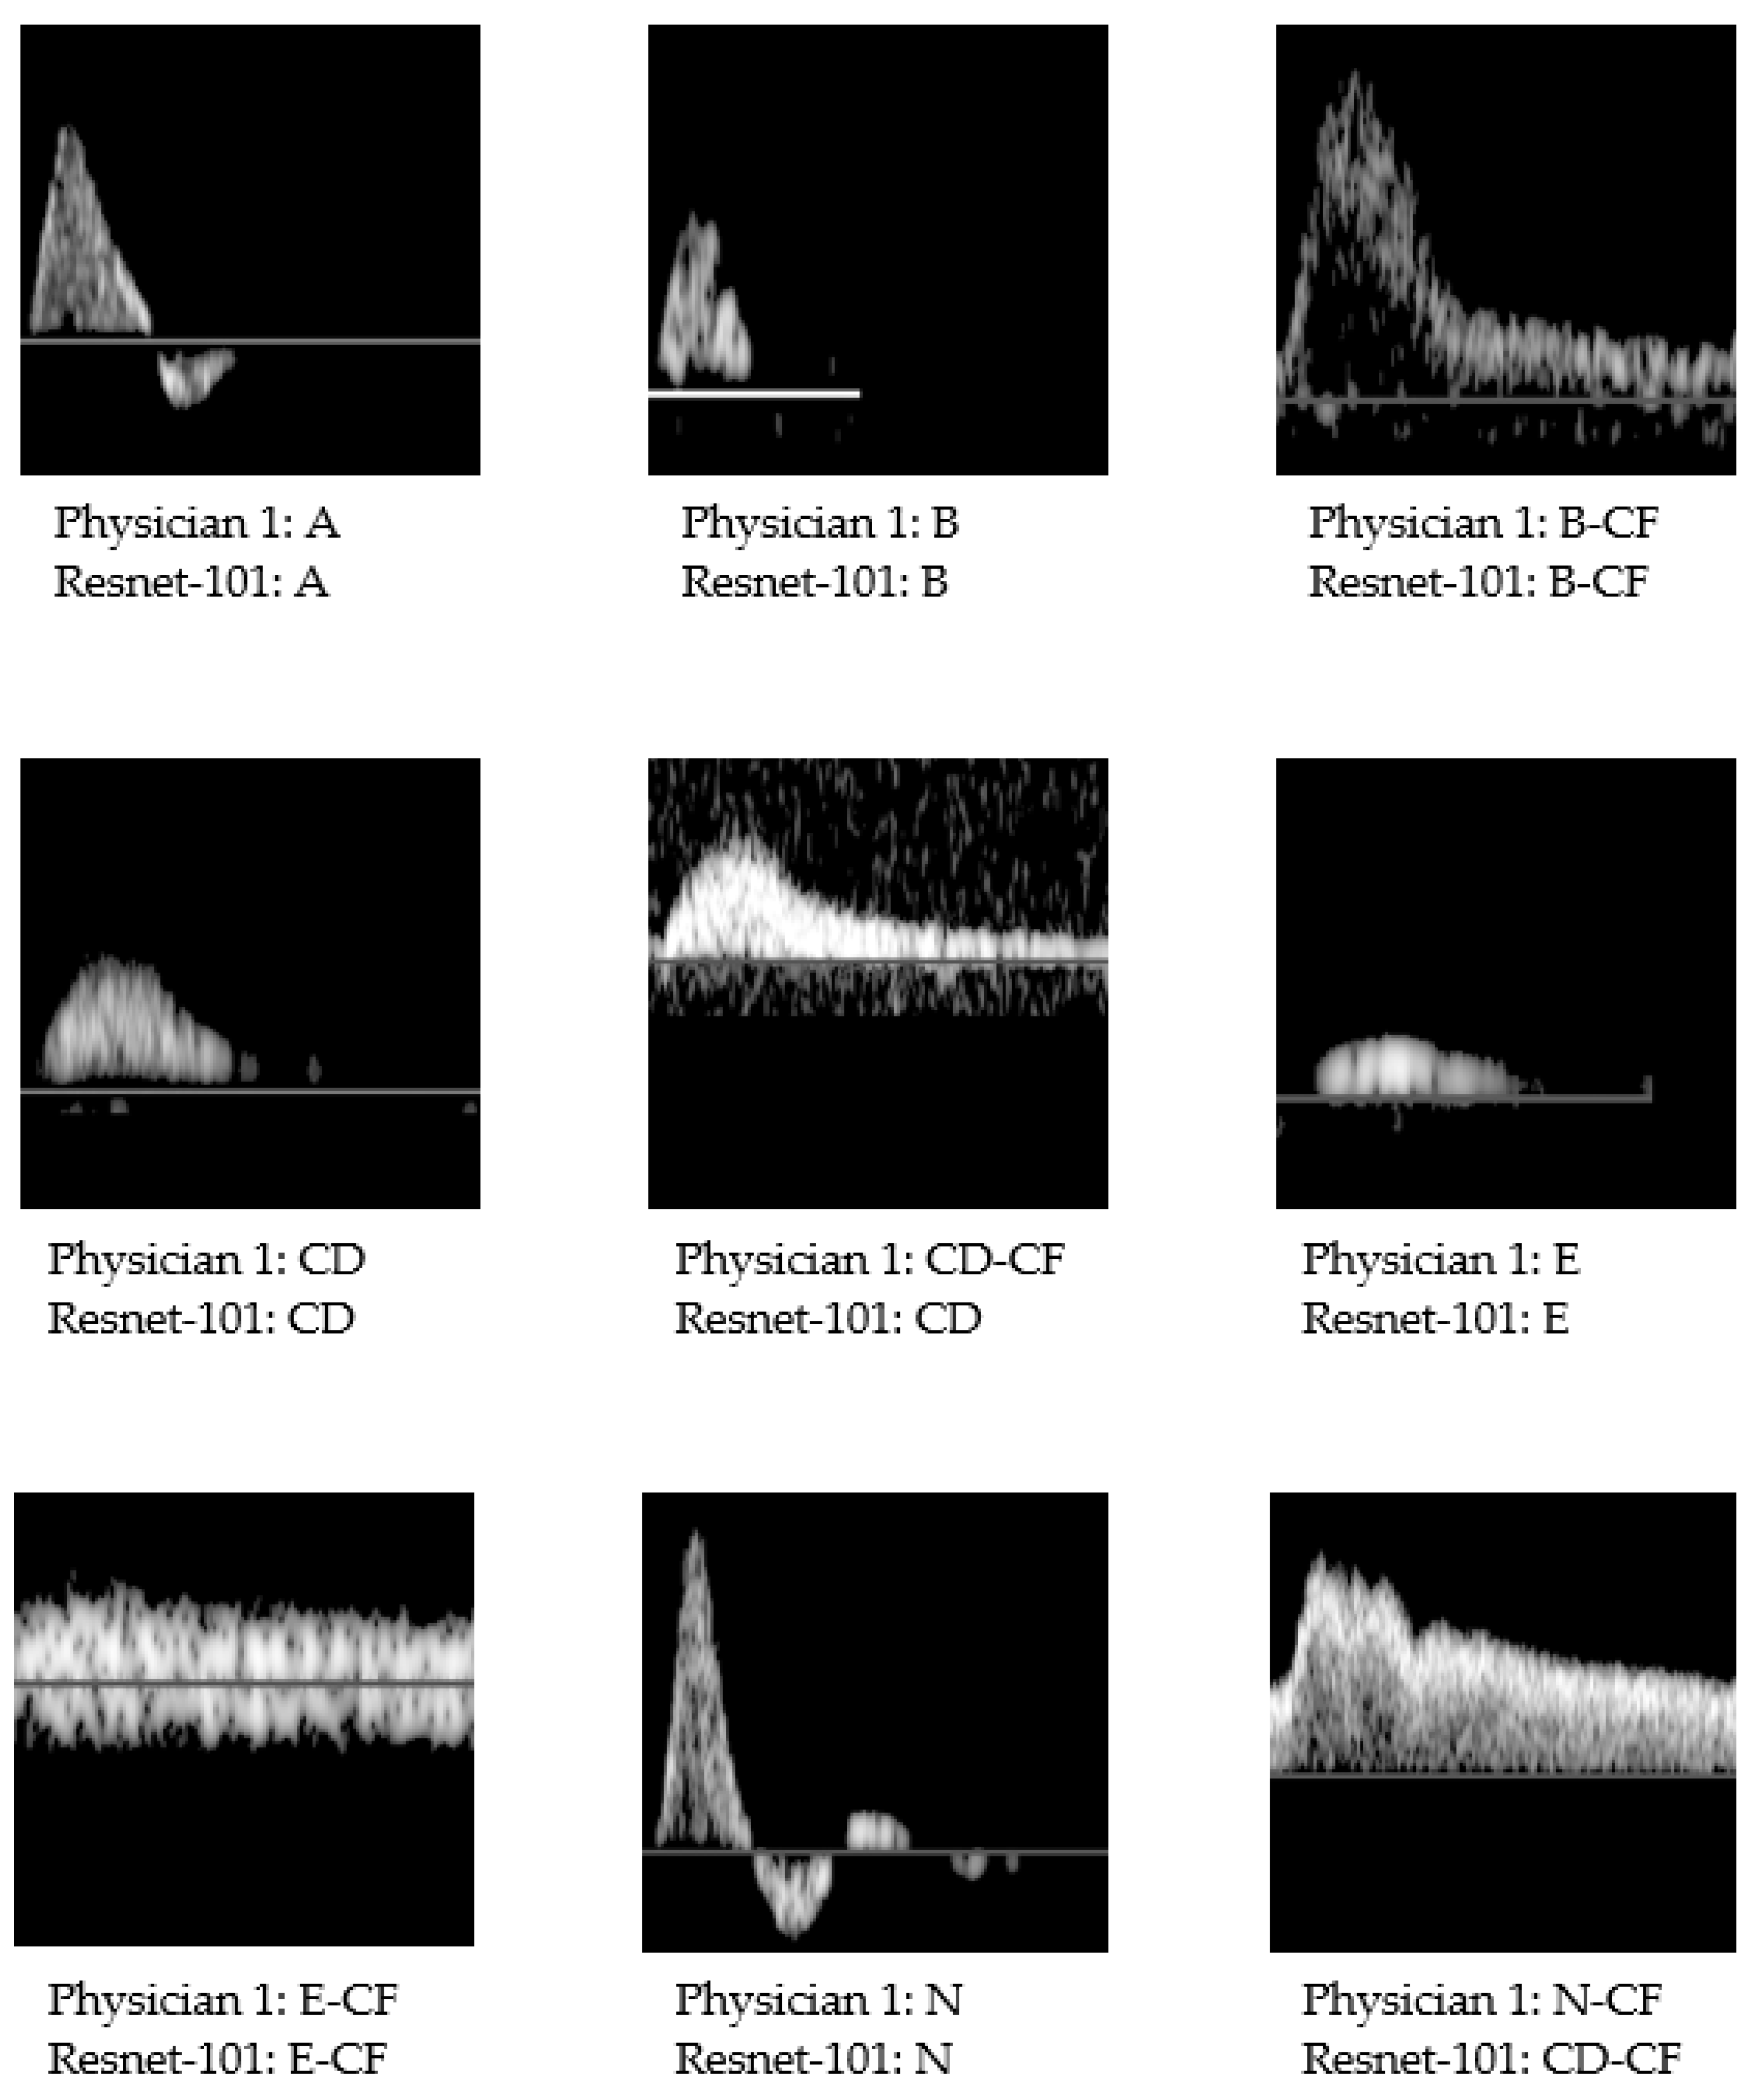

| ResNet-101 | N | N-CF | A | B | B-CF | CD | CD-CF | E | E-CF |

| N | 126 | 1 | 4 | 0 | 0 | 0 | 0 | 0 | 0 |

| N-CF | 7 | 6 | 0 | 0 | 0 | 0 | 1 | 0 | 0 |

| A | 7 | 0 | 118 | 2 | 1 | 1 | 0 | 0 | 0 |

| B | 0 | 0 | 1 | 13 | 0 | 4 | 0 | 0 | 0 |

| B-CF | 2 | 3 | 0 | 1 | 20 | 0 | 4 | 0 | 0 |

| CD | 3 | 0 | 2 | 3 | 0 | 21 | 2 | 2 | 0 |

| CD-CF | 0 | 5 | 0 | 0 | 7 | 1 | 28 | 0 | 1 |

| E | 0 | 0 | 0 | 0 | 1 | 2 | 0 | 10 | 0 |

| E-CF | 0 | 0 | 0 | 0 | 0 | 0 | 0 | 1 | 13 |

| Agreement (%) | 86.9 | 40.0 | 94.4 | 68.4 | 69.0 | 72.4 | 80.0 | 76.9 | 92.9 |